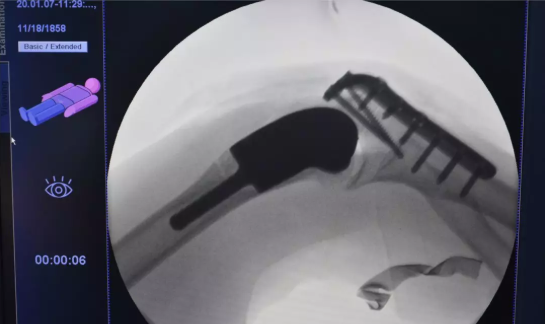

2020年1月7日,上海九院骨科郝永强教授团队利用3D打印技术,为患者樊女士成功实施了右肘肿瘤精准切除和植入了为她“量身定制”的3D打印肘部(肱骨远端)个性化重建假体的手术。“私人定制”的钛合金人工假体帮樊阿姨如愿地保住了完整右上肢,且肘关节功能大为改善。此台手术不仅是1月1日施行《定制式医疗器械监督管理规定(试行)》后完成的第一台定制式医疗器械植入手术,据悉,此前郝永强教授团队在戴尅戎院士带领下已为近200名患者实施了3D打印个性化假体重建手术。

由于右肘关节受血管瘤侵及,现右肱骨远端骨质严重破坏,拟行右肘部肱骨远端肿瘤切除+右肱骨远端个性化假体重建手术,为精准重建切除后的肱骨远端复杂关节骨缺损,为其定制了3D打印个性化肱骨远端假体。